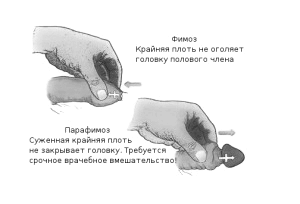

- фимозом,

При набряку і почервоніння голівки, появі хворобливих виразок на ній і крайньої плоті, загальної слабкості та високої температури діагностують гангренозну форму баланопостіта і розвиток фімозу.

- звужується уретра і розвивається фімоз,